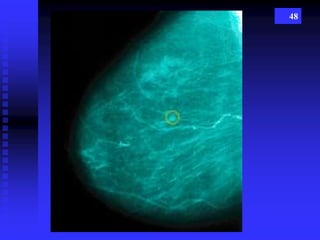

48